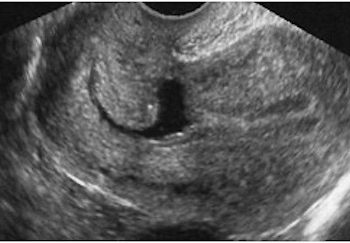

How To Do Febbraio 2024: Istmocele

Cari soci, questo mese un nuovo video "How to do", dedicato allo studio ecografico dell'istmocele Grazie a Daniela Giuliani! Il...